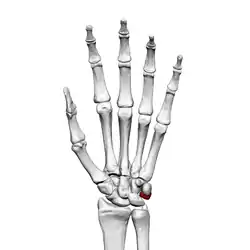

![]() Ліва рука спереду (з боку долоні). Тригранна кістка виділена червоним. | |

Тригранна кістка[2] (лат. os triquetrum) — одна з кісток зап'ястка, належить до проксимального ряду. Гомологічна кістці ulnare плазунів і земноводних, що зчленовується з ліктьовою.

Тригранна кістка має пірамідальну форму, овальною гранню вона зчленовується з горохоподібною кісткою, чотирибічною — з півмісяцевою, вигнутою — з гачкуватою. Розташовується в проксимальному ряді зап'ясткових кісток, на верхньо-ліктьовій стороні зап'ястка[3]. Для полегшення пальпації тригранної кістки при обстеженні кисть слід відвести в променевому напрямку, щоб кістка висунулася з-під шилоподібного відростка.